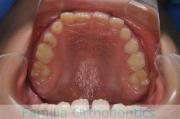

犬歯が八の字になっているので何とかしてほしいということで来院されました。上顎犬歯が左右とも前歯の方に向いていて、一期治療でまずは萌出誘導を行いました。

二期治療は、出っ歯の要素が強かったため、上顎のみ第二小臼歯を抜歯しています。

二期治療は2年強、25回程度の通院が必要でした。犬歯の埋伏歯は、うまく出すことができない場合があったり、出す際に周囲の歯の歯根に傷をつけるリスクがあったりします。